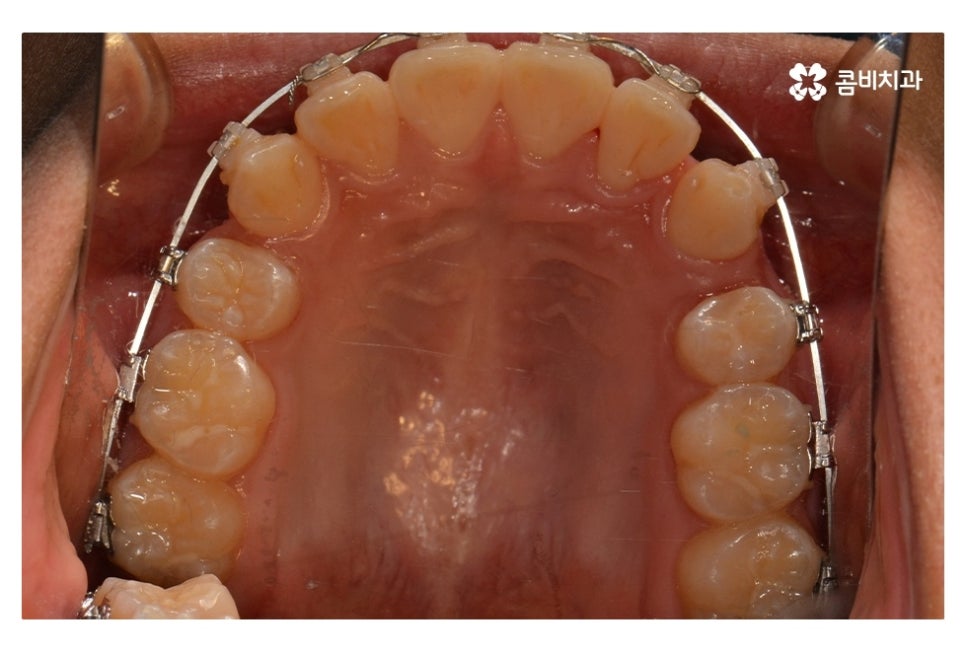

오늘 보여드릴 중학생치아교정 사례의 경우에는

악골의 위치는 정상적인 상태에서 불규칙한 치열로 인해

교정 치료를 진행한 사례라고 할 수 있어요.

위 환자분의 경우 발치가 진행된 사례로 치아의 이동 공간을

고려할 때 발치가 필요했고 환자분도 보다 나은

심미성을 위해서 동의한 상황이라고 할 수 있어요.

위 사진에서 보시면 시간이 지나면서 발치를 했던 치아의

공간이 사라지고 교정을 통해서 치열이 가지런해진 것을 확인할 수 있는데요.